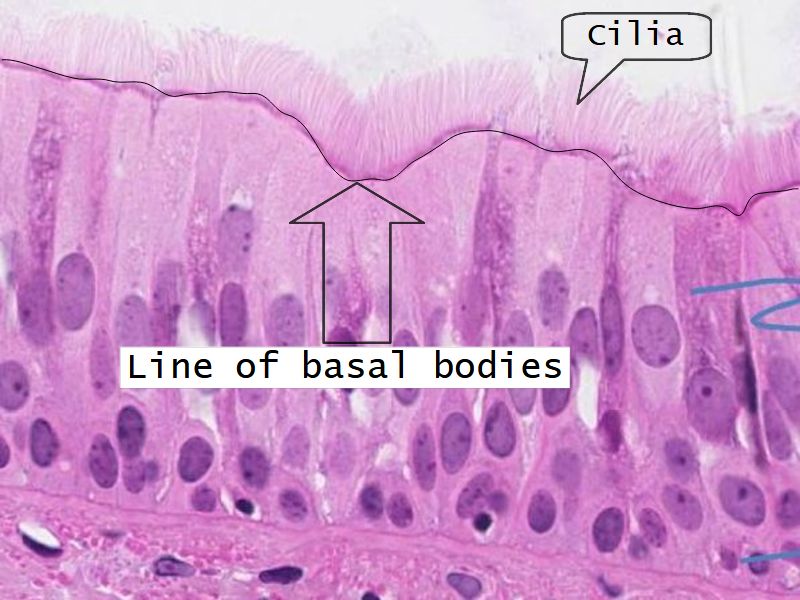

Respiratory epithelium

- Pseudostratified

- Ciliated

- Columnar

- Ciliated columnar cells

- Basal cells